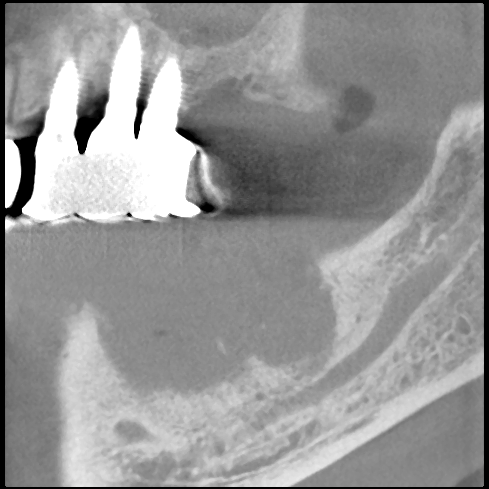

JUGEMテーマ:歯の健康 このレントゲン写真は、二つあった歯根の右側を抜去して、左側を一時的に わざと残した例です。 左側のレントゲン写真は抜いたときのもの。 右側のレントゲン写真は、4ヵ月後のもの。 右側のレントゲン写真では、残した歯根は浮き上がってきています。 そして、その右側の、先に抜いた部分の凹みが緩やかになったのがわかるでしょうか。 歯根をのこして、置くことにより周囲の骨の回復を助けることになるのです。 この方法は、前歯部分でも応用できます。 ...